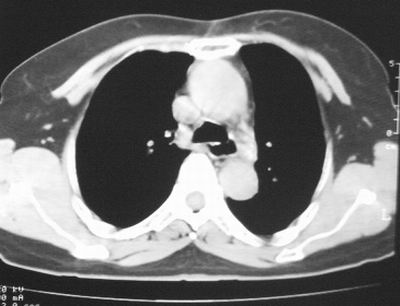

患者,女,64岁,4年前左腮腺"多形性"腺瘤手术治疗史.现复查胸部ct见左下肺块状影,该影与原左腮腺手术是否有联系?

本次复查胸部ct

左下肺软组织块影,有分叶、毛刺、空泡及胸膜牵拉征,左下肺周围性肺癌。

我考虑炎性假瘤:1,边界模糊.2,邻近胸膜增厚,胸膜外脂肪也增厚.3,周围有肺气肿征.4,无胸水,无淋巴结肿大.

左肺下叶周围型肺癌,支持!(软组织肿块+分叶+毛刺+空泡+胸膜凹陷征)

肿块周围提示慢性改变,邻近胸膜外脂肪有沉积,考虑为良性,炎性假瘤可能。

左下肺软组织密度影,可见分叶,边缘可见毛刺征,胸膜增厚,强烈要求左下肺周围型肺癌

左下肺后基底段实性肿块,周围有毛刺,病变周围有肺气肿,与降主动脉间有条带状影相连,病灶4年前查体发现,纵隔内未见肿大淋巴结。考虑.肺隔离症,建议增强扫描与周围型肺癌鉴别。